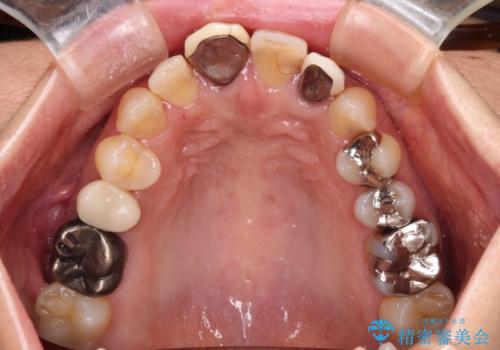

- 保険診療でのクラウンが変色してしまったとのことで来院された患者様です。

根管治療がされていなかったため、まずは根管治療を行い、その後オールセラミッククラウンにて補綴することとしました。

左上の歯も歯肉縁部分にメタルの色が見えており、合わせて治療することをお勧めしましたが、今回は1歯のみを治療することとしました。